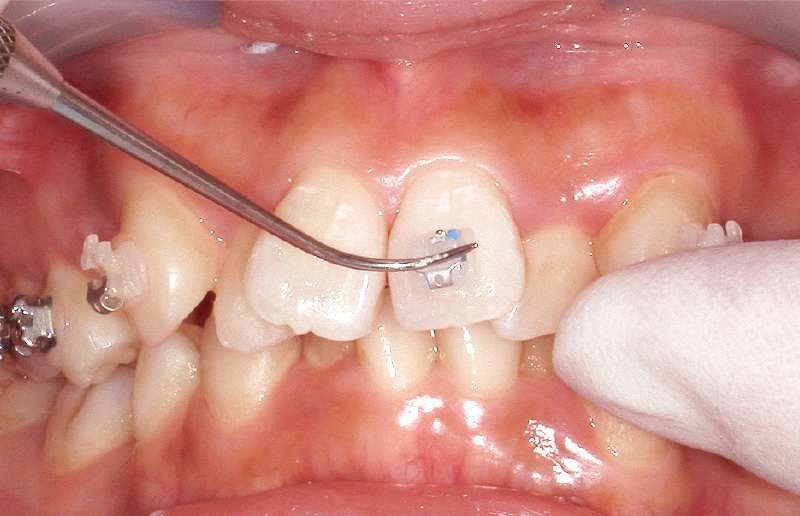

![[写真] 探針で位置を微調整後、圧接](/academic/dentalmagazine/wp-content/uploads/sites/2/2025/11/195-13_photo10.jpg)

図10 探針で位置を微調整後、圧接 -